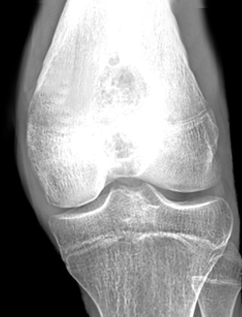

骨・軟部腫瘍とは・・・

骨軟部腫瘍は、骨やその周囲の組織で発生する腫瘍の総称です。

これらの腫瘍はさまざまな形態や原因で発生し、良性または悪性である場合があります。

代表的な骨腫瘍には、骨肉腫、骨髄腫、骨軟骨腫などがあります。

骨の良性腫瘍

- ・骨軟骨腫(Osteochondroma)

- 最も一般的な骨の良性腫瘍の一つで、特に若年者に見られます。

- ・骨嚢胞(Bone cyst)

- 単純骨嚢胞や異骨症など、骨内に液体または半固体の内容物を含む空洞が形成されます。

診断には、画像検査(X線、CT、MRI)、組織生検などが必要です。

治療法は、腫瘍の種類、大きさ、進行度によって異なりますが、手術、放射線療法、化学療法などが一般的に使用されます。